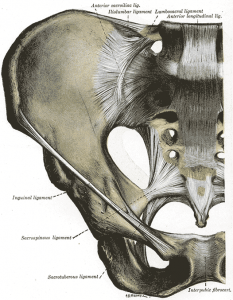

There is an important network of ligaments, which lie at the front and back of the pelvis. These ligaments are very important in Chiropractic, as weakness, tension, or trauma to the ligaments affects function of the joint. Between some of these ligaments passes muscle and nerves, which when compressed can affect local function.

At the front of the pelvis is the pubic symphysis, the anterior (front) connection of the pelvis. The leg bone joins the pelvis at the hip joint.

The sacro-iliac joint (SIJ) consists of the sacrum (the large central triangular bone), and ilium (the large pelvis bone) on the outside. The sacro-iliac joint is important because it essentially forms the base of the spine – the next weight bearing joints above are the lumbar spine (low back), and sacro-iliac joint dysfunction can have effects upwards into the low back, mid back, and neck, and downwards into the knee and ankle.